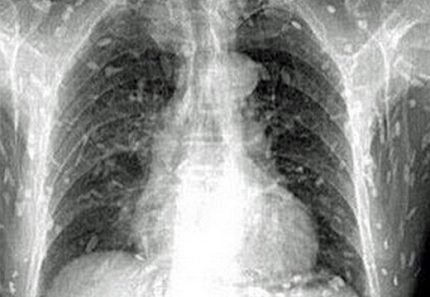

¼¿ï½Å¹® ³ª¿ì´º½º]Æò¼Ò ȸ¸¦ Áñ±â´ø ÇÑ Áß±¹³²¼ºÀÌ ¿À¿°µÈ »ý¼±ÃʹäÀ» ¸ÔÀº ÈÄ ¿Â ¸öÀÌ ±â»ýÃæ¿¡ °¨¿°µÈ Ãæ°ÝÀû »çÁøÀÌ °ø°³µÅ ³í¶õÀÌ Àϰí ÀÖ´Ù.

¹Ì±¹ ¿Â¶óÀÎ ¸Åü ¿ÀÆÛ¡ºäÁopposingviews.com£©´Â ÃÌÃæ£¨tapeworm£©¿¡ ¿Â¸öÀÌ °¨¿°µÈ ÇÑ Áß±¹³²¼ºÀÇ ¿¢½º·¹ÀÌ »çÁøÀ» 24ÀÏ£¨ÇöÁö½Ã°££© °ø°³Çß´Ù.

Áß±¹ ³²ºÎ ±¤µ¿¼º¿¡ °ÅÁÖ ÁßÀÎ °ÍÀ¸·Î ¾Ë·ÁÁø ÀÌ ³²¼ºÀº ÃÖ±Ù ºÎ½ º¹ºÎÅëÁõ°ú ÇǺΠ°¡·Á¿òÁõÀÌ ½ÉÇØÁ® ±¤Àú¿ì Á¦8Àικ´¿øÀ» ã¾Ò´Ù. ÀÌÈÄ ¿øÀκм®À» À§ÇØ ÃÔ¿µµÈ ÇØ´ç ³²¼ºÀÇ ¿¢½º·¹ÀÌ »çÁøÀ» º» ÀÇ·áÁøÀº °øÆ÷¿¡ °¡±î¿î ±âºÐÀ» ´À²¼´Ù. ÇØ´ç ³²¼ºÀÇ ¿Â ¸ö ±¸¼®±¸¼®¿¡ ¼¿ ¼ö ¾øÀ» Á¤µµ·Î ¸¹Àº ÃÌÃæµéÀÌ ±â»ýÇϰí ÀÖ¾ú±â ¶§¹®ÀÌ´Ù.

º´¿ø Ãø¿¡ µû¸£¸é, ÀÌ ³²¼ºÀº Æò¼Ò »ý¼±È¸¡¤ÃÊ¹ä µîÀ» ¹«Ã´ Áñ°Ü¸Ô¾ú´ø °ÍÀ¸·Î ¾Ë·ÁÁ³´Ù. ÀÇ·áÁøÀº ÀÌ ³²¼ºÀÌ ¿À¿°µÈ »ý¼±ÀÌ »ç¿ëµÈ ÃʹäÀ» Á¦´ë·Î ÀÎÁöÇÏÁö ¸øÇÑ Ã¤ Áö¼ÓÀûÀ¸·Î ¼·ÃëÇÏ¸é¼ ÀÌ¿Í °°Àº ´ë·® ±â»ýÃæ °¨¿°¿¡ ½Ã´Þ¸®°Ô µÈ °ÍÀ¸·Î ºÐ¼®Çß´Ù.